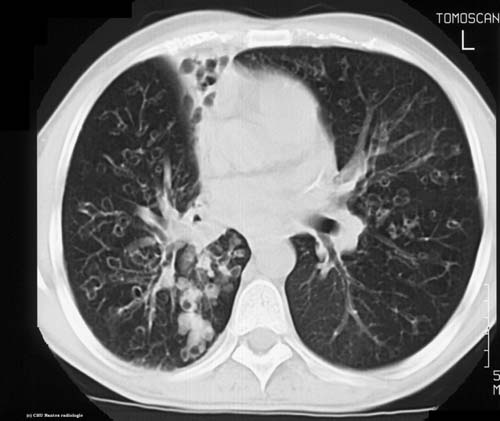

TDM

niveau de la coupe